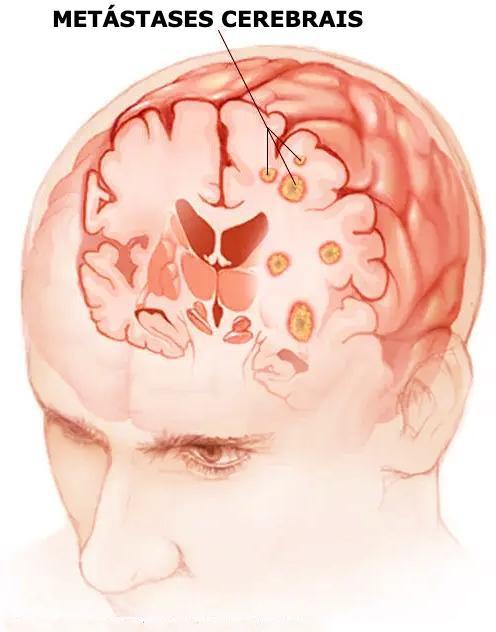

Metástases Cerebrais

- Localização Predominante: áreas altamente vascularizadas, como os hemisférios cerebrais (85%), cerebelo (10-15%) e tronco encefálico (5%).

- Efeitos no SNC: alteram a função neurológica devido ao efeito de massa, edema vasogênico e inflamação local.